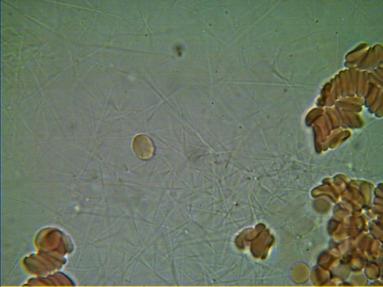

Podaję teraz przykładowe obrazy krwi

2.PASOŻYTY I GRZYBY

w zakwaszonym środowisku rozwijają się różnego rodzaju organizmy pasożytujące : robaki, grzyby, bakterie, wirusy i inne. Walka z nimi jest możliwa tylko przez zmianę środowiska z kwaśnego na zasadowe, w tym środowisku nie mogą się one rozmnażać i żyć.

We krwi widoczne są larwy i jaja pasożytów.

Komórki grzybów. W zależności od tego w jakim stopniu organizm zaatakowany jest przez grzyba widoczny jest obraz pojedynczych komórek lub całych kolonii i wtedy możemy mówić o bardzo niebezpiecznej dla organizmu grzybicy.